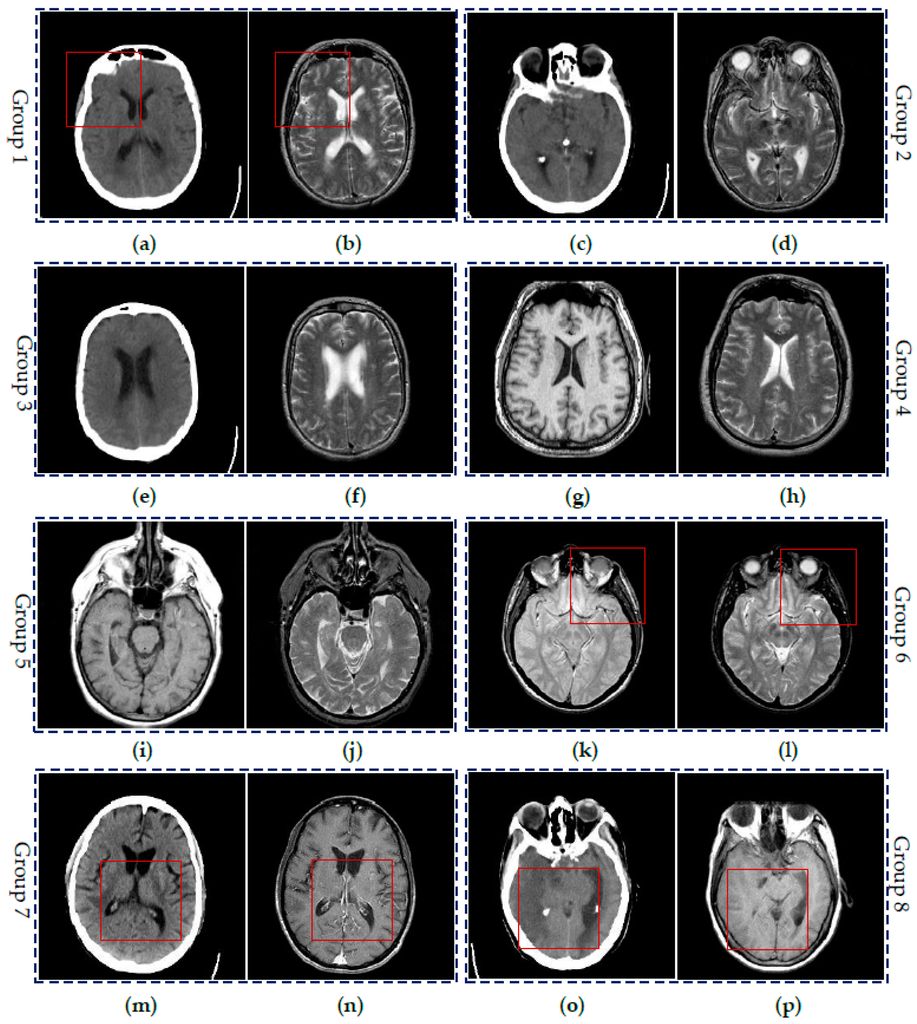

4.2. Visual Comparisons of Fused Results